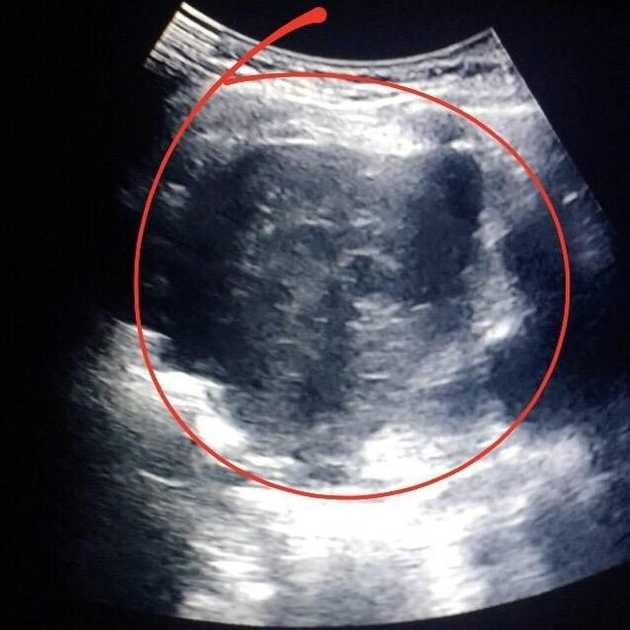

Still practicing what I learned from the wellness facility, I finally gave in to surgery after I had a chest ultrasound, after I saw in the monitor the large tumor near to my beating heart.

Chest Ultrasound